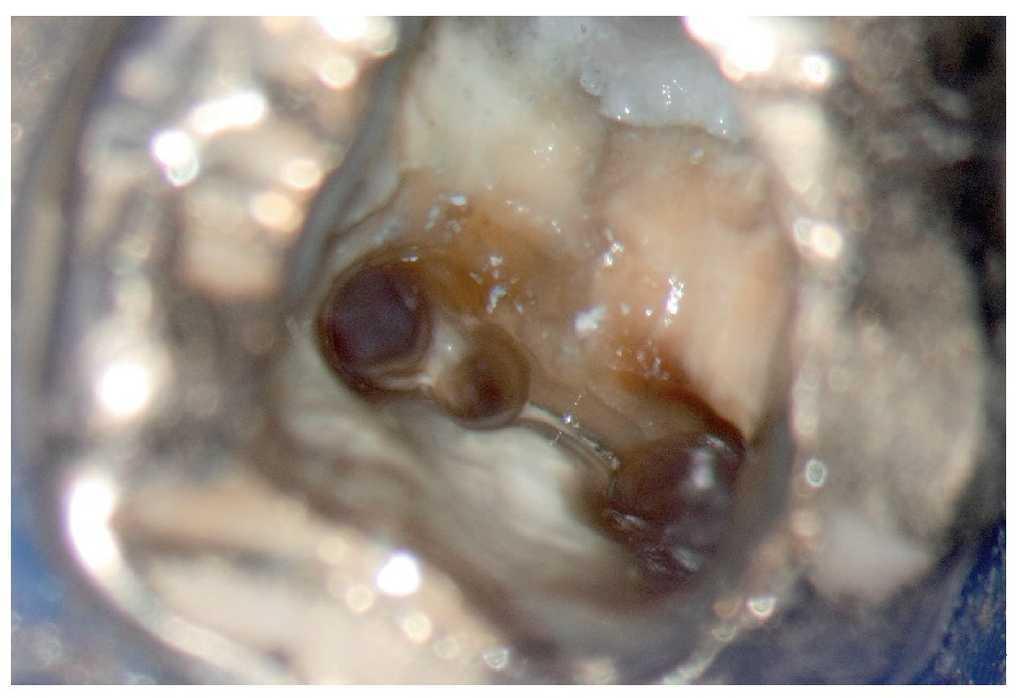

Figura 9f. Eliminación de la capa de cemento en apical del lugar de introducción del perno.

Figura 9g. Visión directa sobre el ápice abierto.